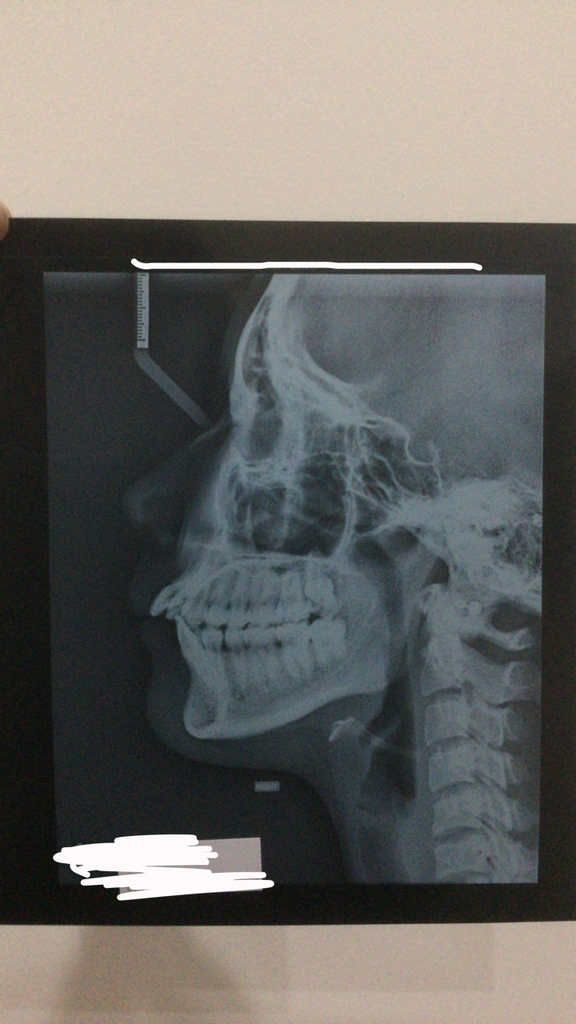

Okay so I went to my ortho today, he was looking at my teeth, said all the right things (crowding, 9mm overjet, severe class 2 malocclusion, crossbite),

Anyways I underwent an OPG and a Cenograph, these are the results.

Anyways I underwent an OPG and a Cenograph, these are the results.